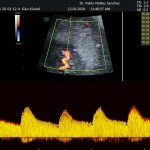

- La vitalidad fetal (Doppler fetal).

- El Doppler de las arterias uterinas maternas y determinación de riesgo y prevención para pre eclampsia severa.